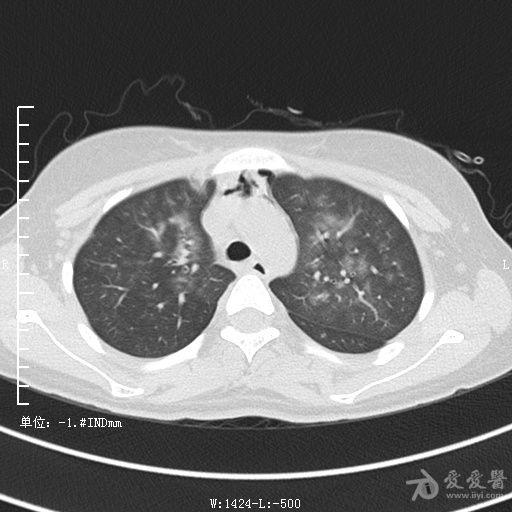

典型支气管扩张及肺水肿CT片

典型支气管扩张肺水肿